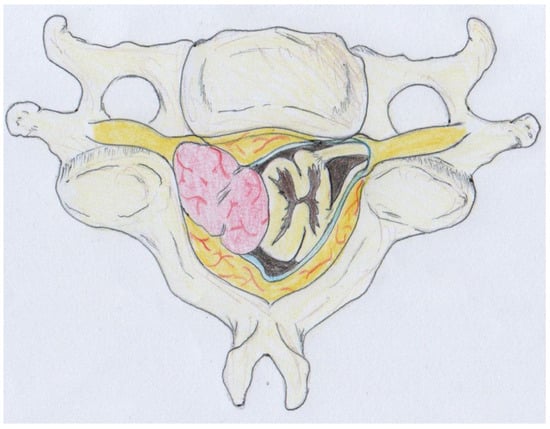

This approach facilitated a safe surgical route despite the tumor’s size, which was causing gradual spinal cord displacement (Figure 5).

Figure 5.

Illustration demonstrating the presence of the intradural extramedullary tumor causing gradual displacement of the spinal cord. Despite the tumor’s size, the surgical approach facilitated a safe route for intervention. Histological examination documented a schwannoma showing degenerative changes and diffuse hypocellular ischemic areas (ancient schwannoma).